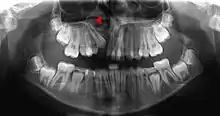

Human jaws with anterior (frontal) portion of alveolar processes cut away towards right | |

The density of the alveolar bone in a given area also determines the route that dental infection takes with abscess formation, as well as the efficacy of local infiltration during the use of local anesthesia. In addition, the differences in alveolar process density determine the easiest and most convenient areas of bony fracture to be used, if needed during tooth extraction of impacted teeth.[22]

The radiographic integrity of the lamina dura is important in detecting pathological lesions. It appears uniformly radiopaque (or lighter).[8]